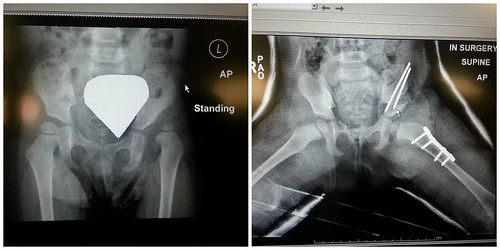

We also got a look at the x-rays to see what they had done. Once she was okay we headed up to the room and tried to help make her comfortable. She was clearly confused and upset about the IV in her hand and other wires and tubes attached to her. I thought she would go to sleep fairly quickly, but she just continued to look around confused about what was going on. After a bit Mike decided to go and pick up the girls from Laura’s house so he could bring them back to see her. Dani fell asleep and I settled in with a book when all of a sudden leaves and tree branches started to hit the windows. I looked out and then closed all the shades because the sound had woken her up. The next thing I knew the PA system started beeping and they asked everyone to please stay away from the windows because of the storm. A few minutes later the PA system beeped again and said, “CODE BLACK CODE BLACK Everyone out of their rooms.”